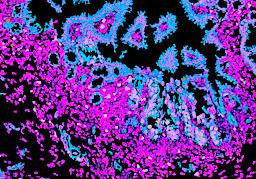

Pancreatic ductal adenocarcinoma is a lethal disease with limited treatment options and poor survival. We studied 83 spatial samples from 31 patients (11 treatment-naïve and 20 treated) using single-cell/nucleus RNA sequencing, bulk-proteogenomics, spatial transcriptomics and cellular imaging. Subpopulations of tumor cells exhibited signatures of proliferation, KRAS signaling, cell stress and epithelial-to-mesenchymal transition. Mapping mutations and copy number events distinguished tumor populations from normal and transitional cells, including acinar-to-ductal metaplasia and pancreatic intraepithelial neoplasia. Pathology-assisted deconvolution of spatial transcriptomic data identified tumor and transitional subpopulations with distinct histological features. We showed coordinated expression of TIGIT in exhausted and regulatory T cells and Nectin in tumor cells. Chemo-resistant samples contain a threefold enrichment of inflammatory cancer-associated fibroblasts that upregulate metallothioneins. Our study reveals a deeper understanding of the intricate substructure of pancreatic ductal adenocarcinoma tumors that could help improve therapy for patients with this disease.